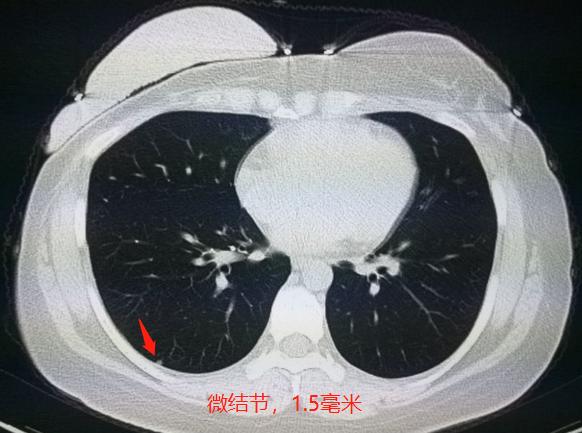

在术后一整年的时候,复查胸部CT发现右下肺微结节,不够2毫米:

1.5毫米的微结节,会不会是转移呢?会不会是新发的肺癌呢?会不会只是小淋巴结呢?

不好说!太小了,没有特征性,也无法通过穿刺确诊(体积太小),化验肿瘤标志物也正常。